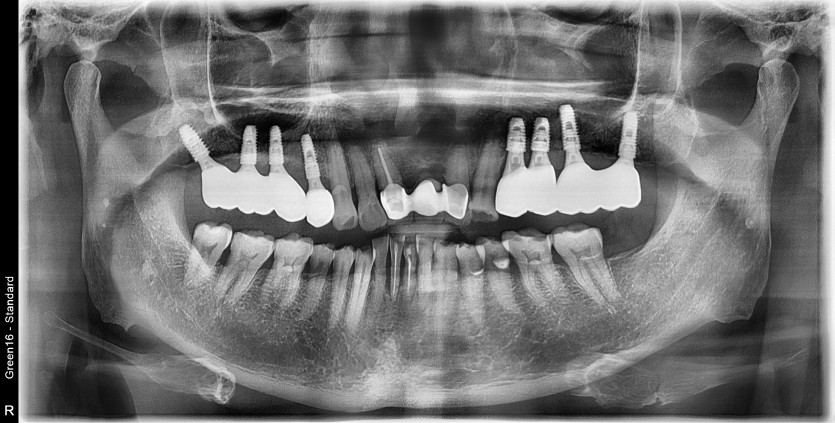

#24.25 타원임플란트 제거 후

임플란트 재수술 + 치조골 이식술 시행하였습니다.